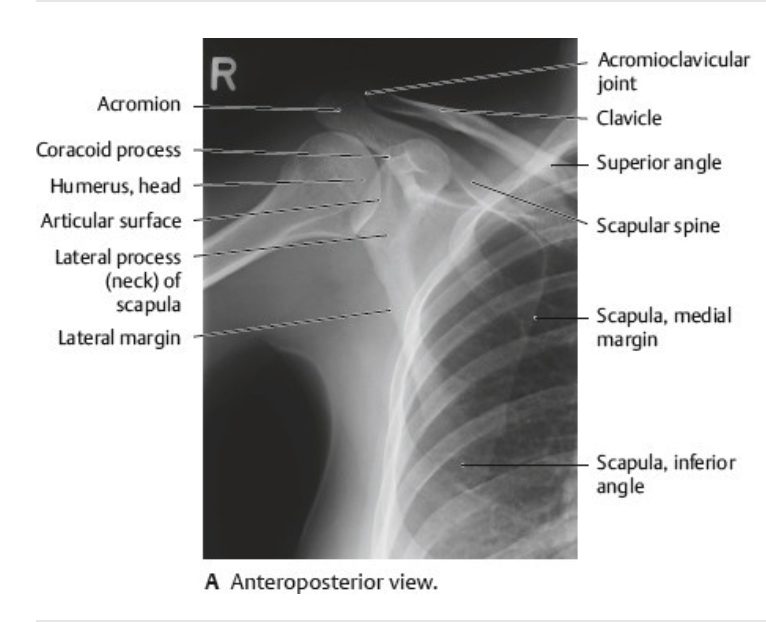

Landmarks of the scapula include the __, the __ process, __ and __ angles, the __ and __ and lateral borders

Landmarks of the scapula include the acromion, the coracoid process, superior and inferior angles, the spine and medial and lateral borders

Pectoral girdle: 2 bone components - clavicle and scapula

Clavicle articulates at the ___ joint

Clavicle articulates at the acromioclavicular joint